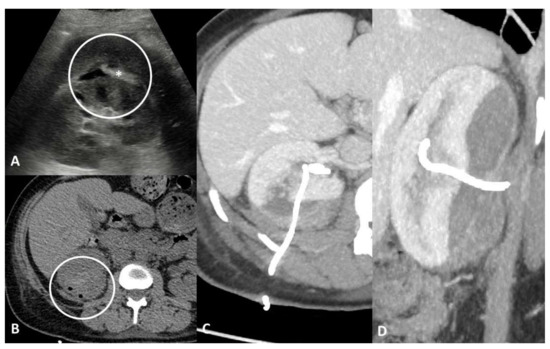

4.1. Vascular Injury

4.2. Parenchymal/Tissue Injury